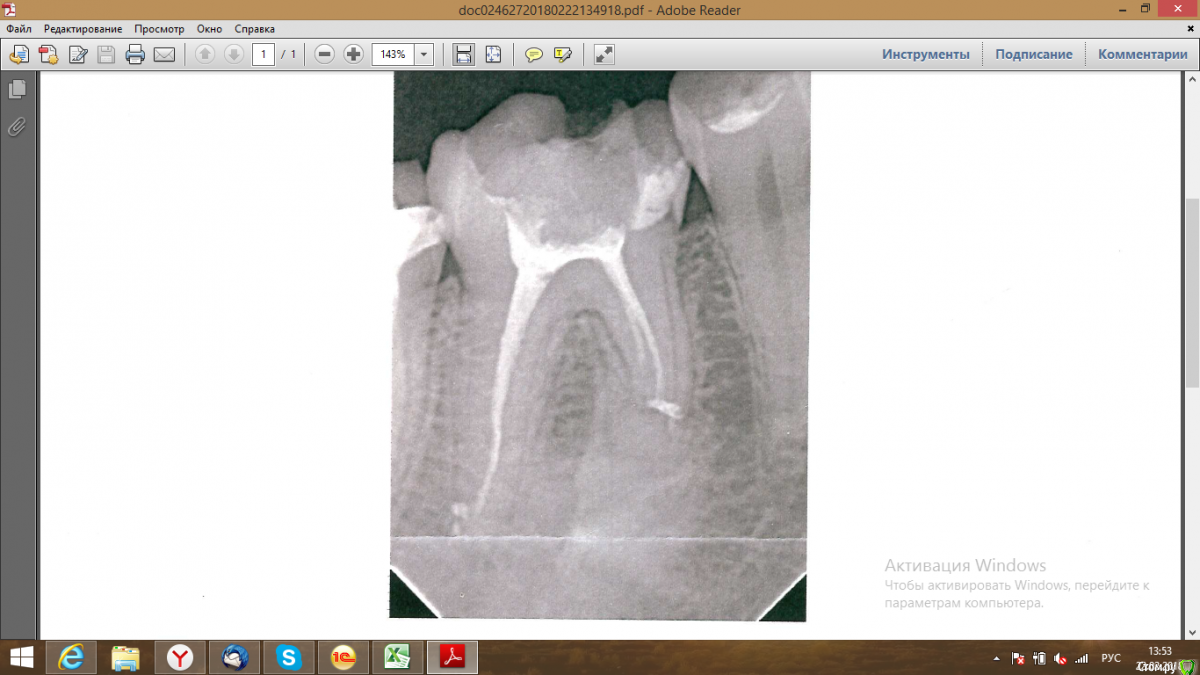

kat_zadorozhnaya Опубликовано 22 февраля, 2018 Автор Поделиться Опубликовано 22 февраля, 2018 Зуб пролечен, лечили без анастезии. Во время пломбирования одного из каналов почувствовала боль, теперь со вчерашнего дня зуб так и ноет. На хол/гор не реагирует, только ноющая боль и невозможность на нём жевать. Скажите, это нормальная ситуация? фото прилагаю. Болит нещадно. После закладки пасты для удаления нерва в прошлую субботу он так же болел, но во вторник прошел, а вот после лечения каналов заболел вновь(((( Ссылка на комментарий